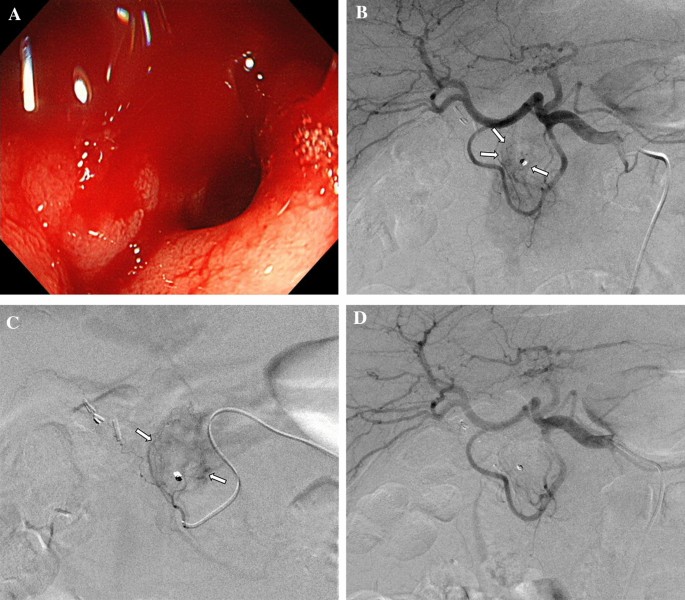

Clinical Insights: Angiographic Findings and Their Impact

Angiography plays a key role in mapping out the vascular supply related to the bleeding sites. It offers clinicians a peek at the fine points that can guide the intervention. In studies conducted over a span of twelve years, angiographic findings consistently revealed traits such as vascular tortuosity, hypervascularity around the bleeding area, and even the presence of microaneurysms in some patients.

These detailed images empower clinicians to make informed decisions during the procedure. For instance, pinpointing a pseudoaneurysm can be particularly important because of its potential to spur recurring hemoptysis. In such cases, additional care is necessary to ensure that the embolic material reaches the exact problematic vessel without spilling over to healthy tissue.

A summary list of key angiographic features includes:

- Vascular Tortuosity: Indicates twisted and looping arteries that may require careful catheter navigation.

- Peripheral Hypervascularity: Suggests increased vessel formation around the bleeding site.

- Microaneurysm Formation: Small dilations that can be linked to recurring bleeding episodes.

- Systemic-Pulmonary Shunts: Abnormal connections that can complicate the clinical picture.